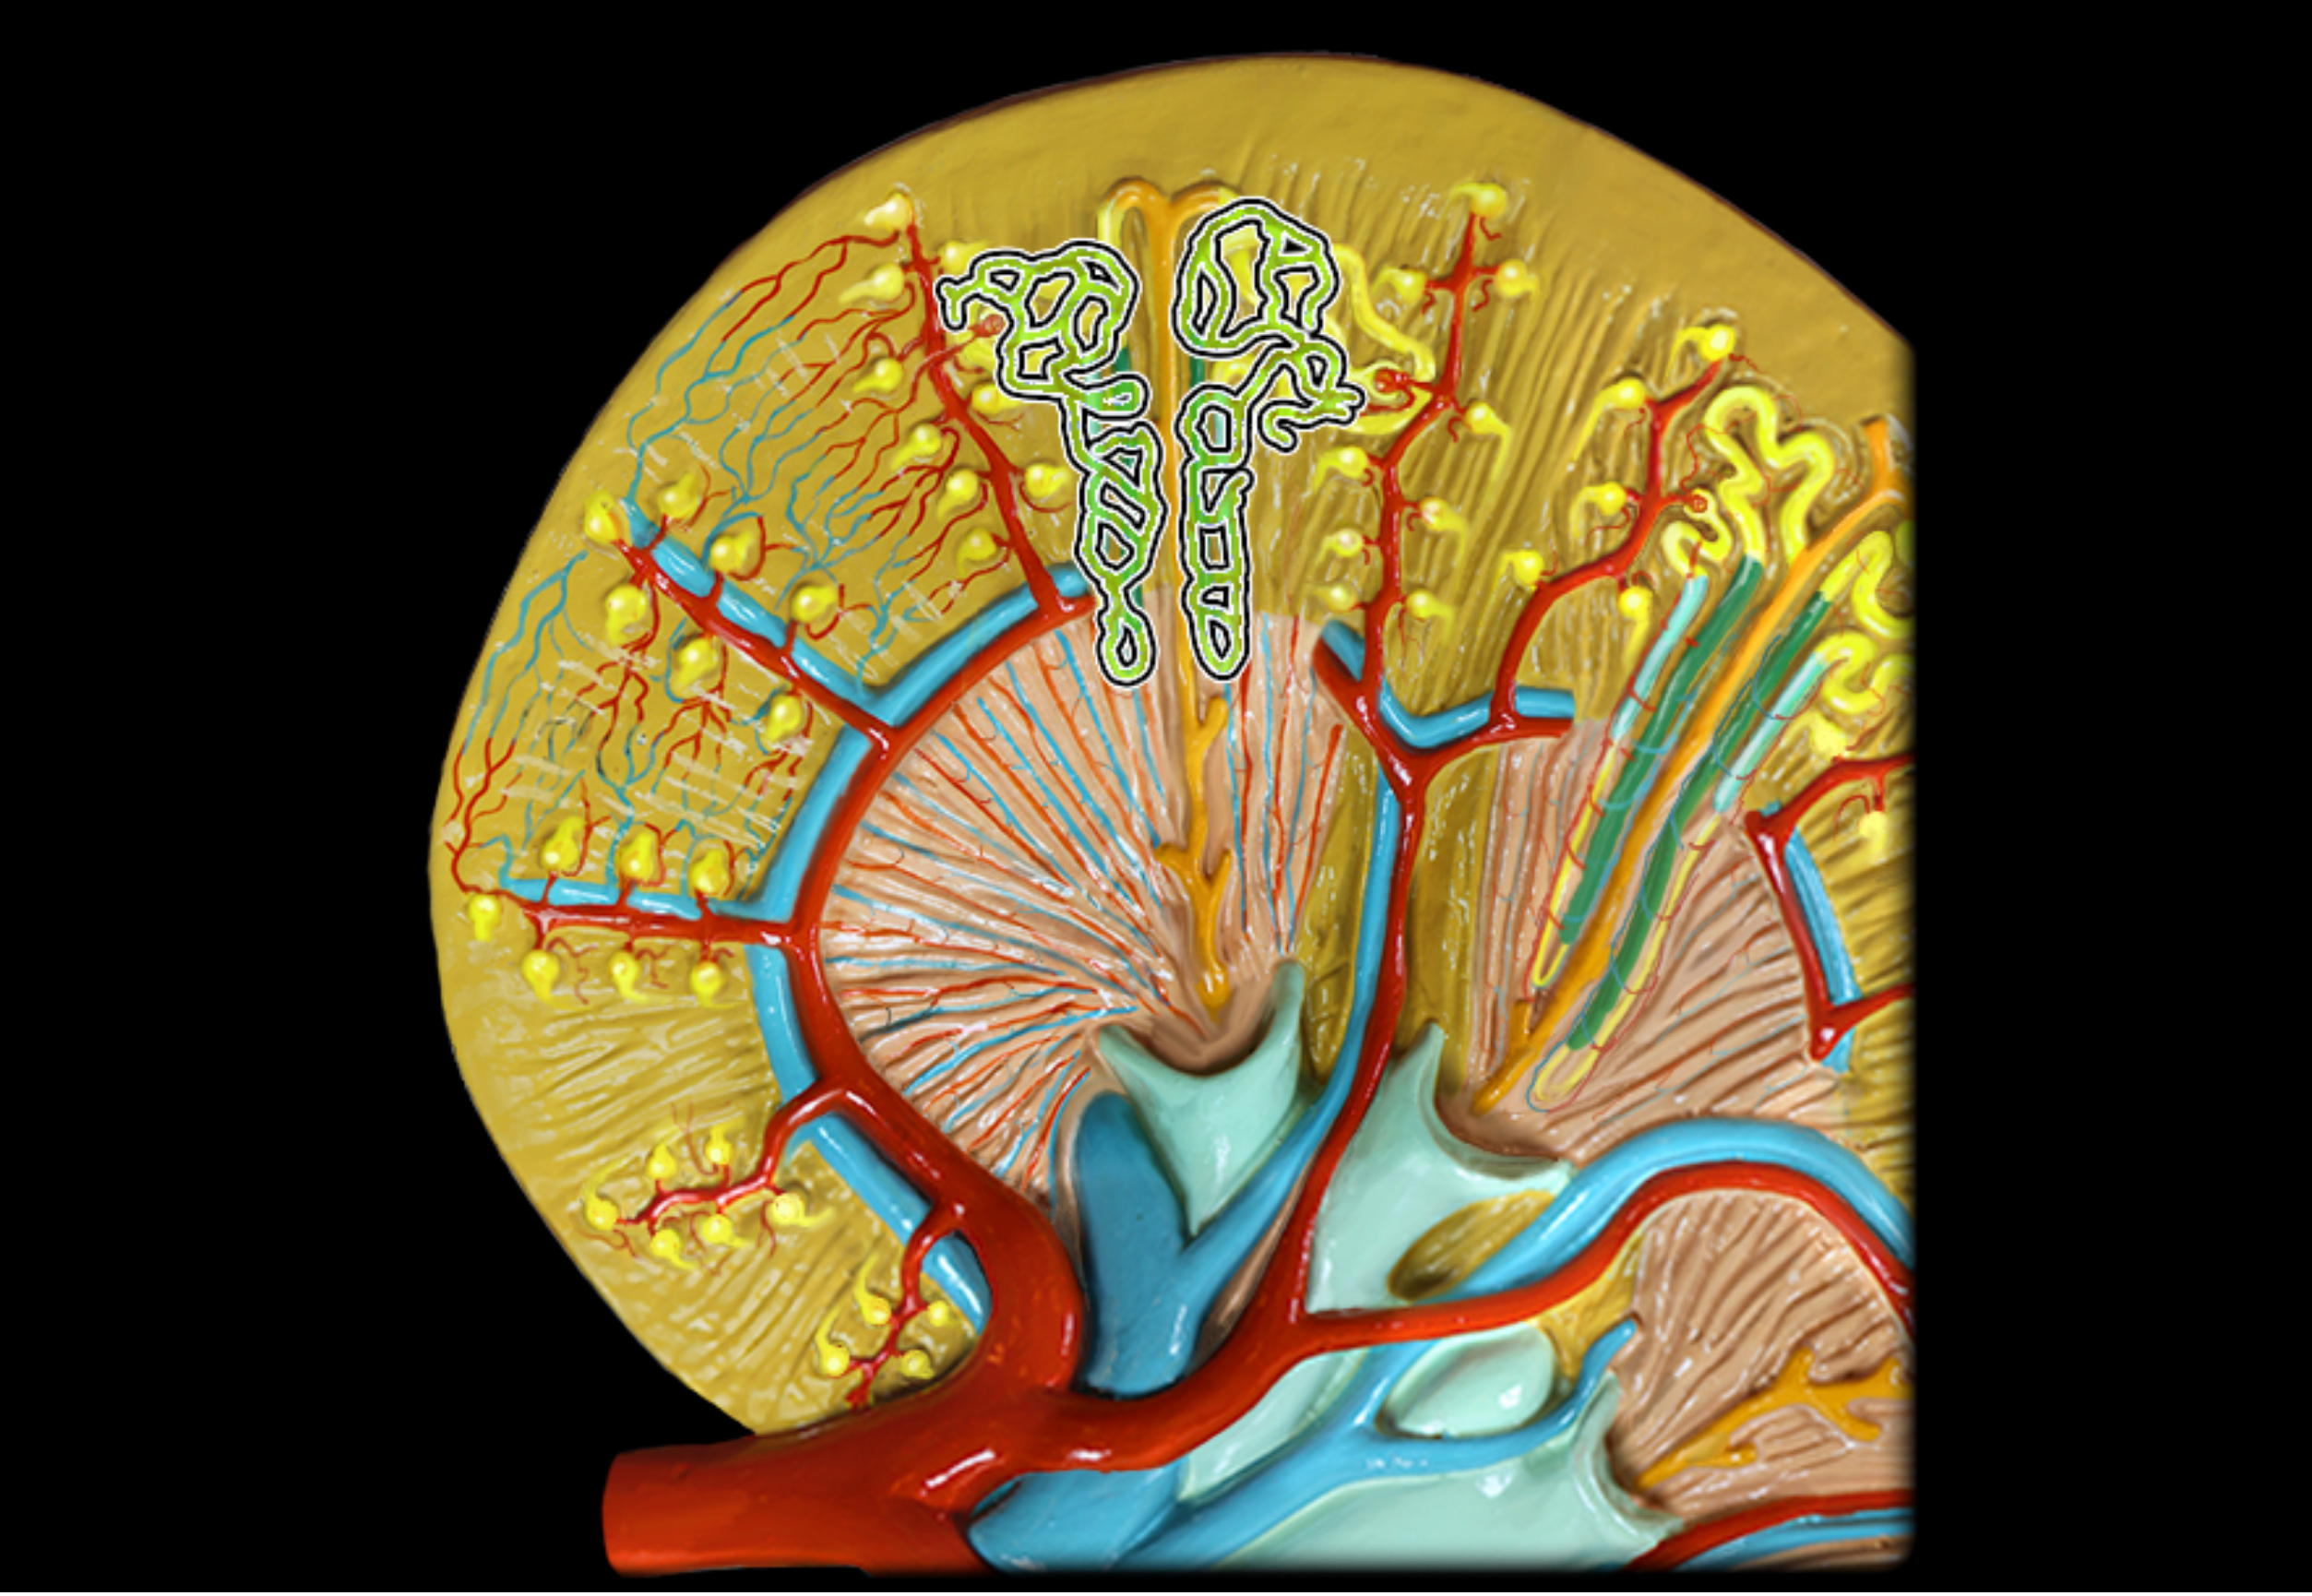

Peritubular capillaries

vasa recta

Renal corpuscle

bowmans capsule + glomerulus